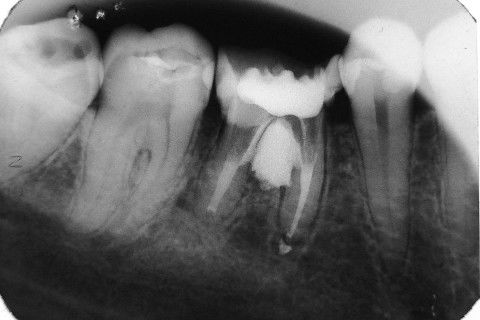

Retratamento de Canal, Tratamento de Perfuração, Restauração Provisória com Resina, Núcleo e Provisório.

RETRATAMENTO DE CANAL, TRATAMENTO DE PERFURAÇÃO, RESTAURAÇÃO PROVISÓRIA COM RESINA, NUCLEO E PROVISÓRIO.